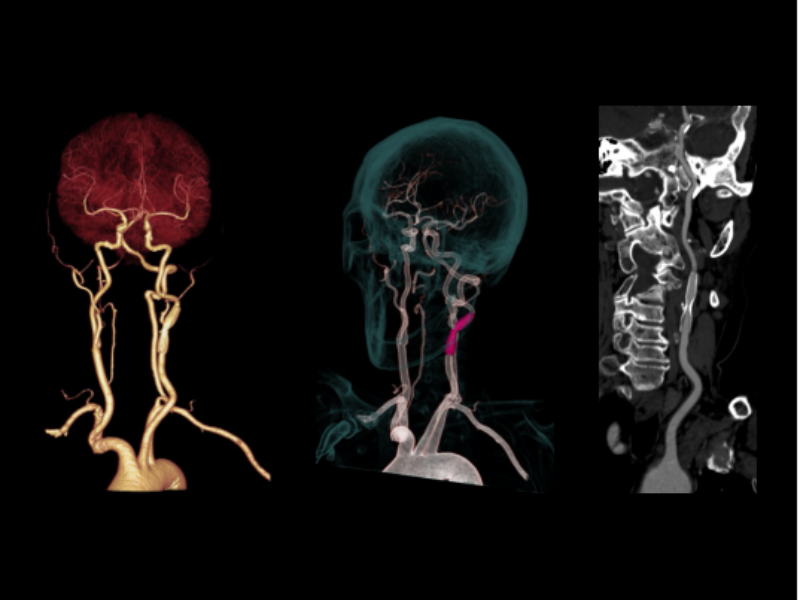

Carotid CTA